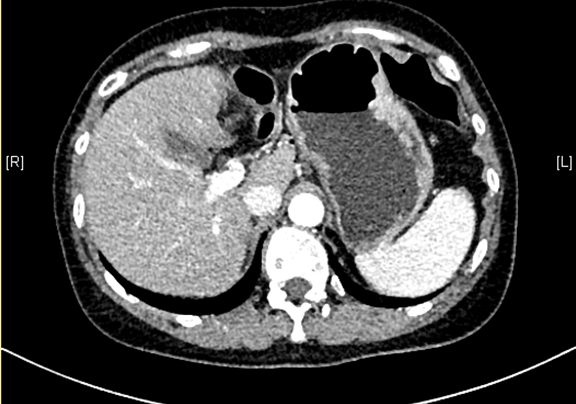

下腹部增强CT示:肝左外叶肝癌可能性大; 肝左内叶及右后叶海绵状血管瘤可能性大。

术前CT检查:

动脉期

静脉期

平衡期